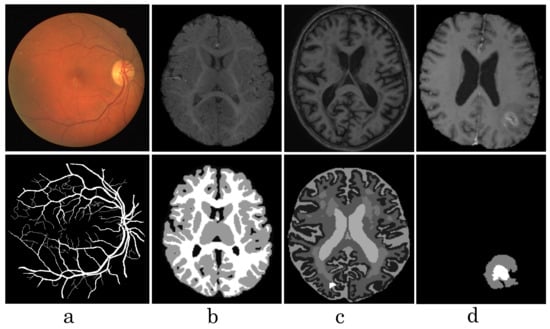

Our observations on medical images are as follows: (i) Boundary information plays a significant role in many medical analysis tasks, such as shape-based cancer analysis, size-based volume measure. (ii) Medical images contain weak boundaries which make segmentation tasks much more challenging due to low intensity contrast between tissues, and intensity inhomogeneity. For example, the myelination and maturation process of the infant brain, the intensity distributions of gray matter (GM) and white matter (WM) have a larger overlapping, and thus, the boundary between GM and WM is very weak, leading to a difficulty for segmentation. (iii) In the medical image segmentation problem, imbalance-class data are naturally existing. Those two challenges of the imbalanced-class data and the weak boundary object in medical imaging are visualized in Figure 1 and demonstrated in Figure 2. Figure 2 illustrates the imbalanced-class problem in medical images through the statistical class distribution of four different datasets. For each dataset, the number of samples between classes are varied. Figure 3 shows statistical values of Mean/Std/Median of pixel intensity in individual class when pixel values are in [0, 1]. Within an individual dataset, the difference between classes in term of Mean/Std/Median is very small. Strong correlation between classes makes the problem of distinguishing classes more challenging, especially at the boundary as shown in Figure 1. This is known as weak boundary problem.

Figure 1. Visualization of some medical images from different datasets, such as DRIVE (a), iSeg17 (b), MRBrainS18 (c), Brats18 (d). The first row shows raw input images, the second row shows labeled images.